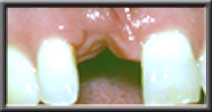

Deficient ridge making artificial tooth look unnatural |

Ridge augmented and expanded so artificial tooth appears to emerge from gum |